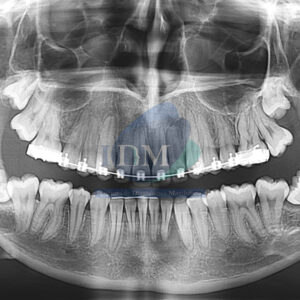

Paciente masculino de 16 años de edad, es referido al Instituto de Diagnóstico Maxilofacial – IDM para evaluación general. En la radiografía panorámica (Figura 1),

Paciente masculino de 30 años de edad, es referido al Instituto de Diagnóstico Maxilofacial – IDM para evaluación general. En la radiografía panorámica (Figura 1),

Paciente masculino de 64 años acude al centro imagenológico para una tomografía computarizada cone beam para una evaluación general. Radiografia Panorámica A la evaluación de

Paciente femenino de 18 años acude al Instituto de Diagnóstico Maxilofacial (sede Miraflores) para evaluación generalizada. Radiografia Panorámica A la evaluación de la radiografía panorámica se